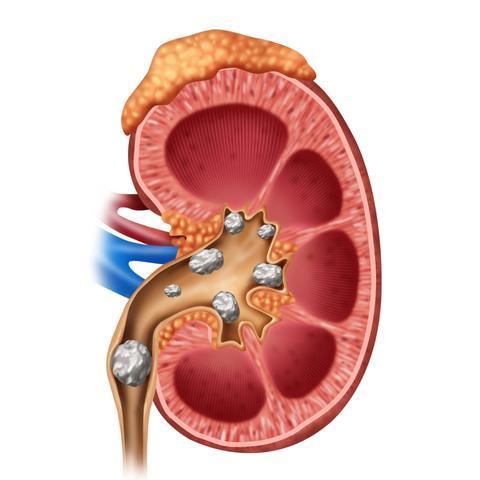

豆角中的嘌呤含量解析,高不高?探讨真相!

作为一名博客站长,我经常收到各种关于食物营养成分的问题,最近有一个问题特别引起了我的注意:“豆角含嘌呤高吗?”我们就来一起探讨一下这个问题。豆角的营养价值豆角是一种常见的蔬菜,富含蛋白质、纤维素、维生素和矿物质等多种...